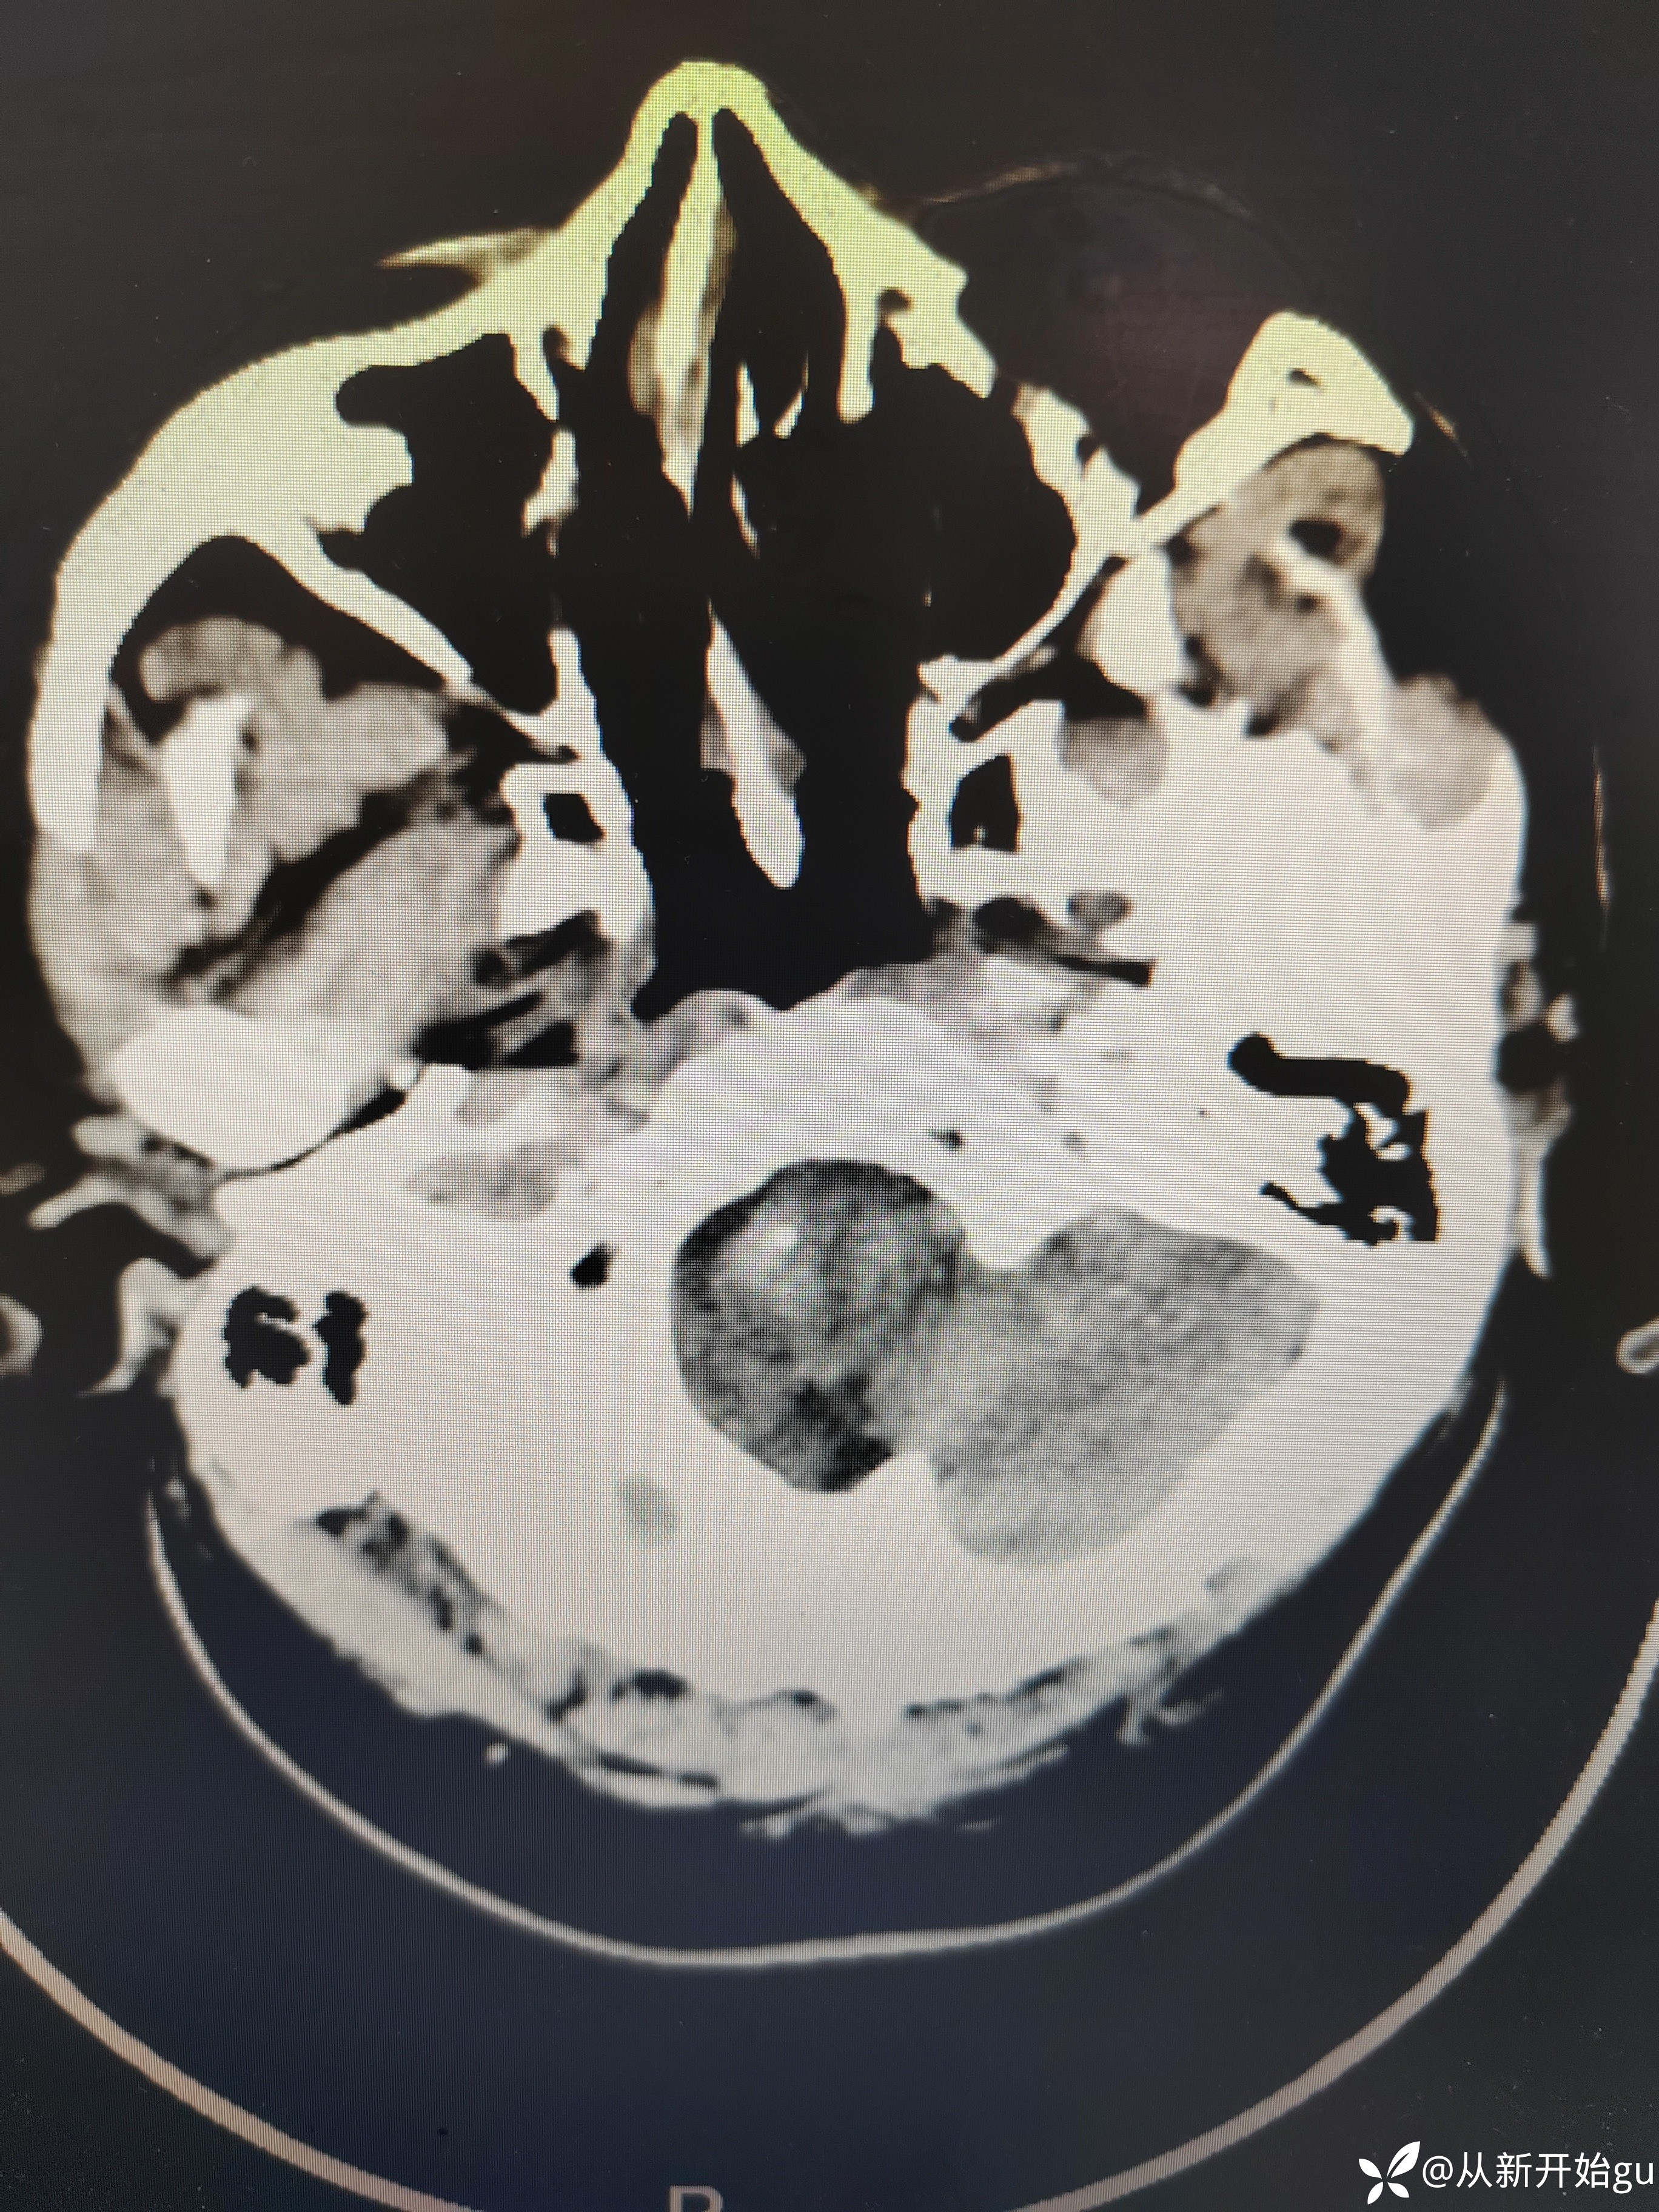

【检查】:完善颅脑CT.

【检查】:完善颅脑CT.